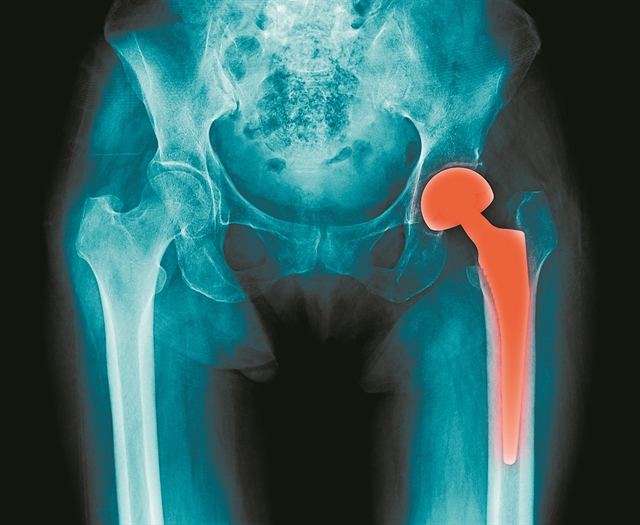

Με αυτή τη λογική, πριν από δέκα ημέρες, οι δημοσιογράφοι τριών μεγάλων εφημερίδων («Le Monde», «The Guardian» και «Süddeutsche Zeitung» δημοσίευσαν μια έρευνα που αφορά τα εμφυτεύματα κάθε είδους (σε γοφούς, γόνατο, καρδιά, στήθος κ.λπ.) που για διαφορετικούς λόγους προκάλεσαν πόνους και ανάγκη για διορθωτικές επεμβάσεις. Ερεύνησαν λοιπόν αφενός τον τρόπο που προωθούν τα προϊόντα τους οι εταιρείες και τη λειτουργία των ελεγκτικών μηχανισμών. Η FDA είναι υπεύθυνη για τους ελέγχους στην Αμερική, αλλά ο αντίστοιχος Ευρωπαϊκός Οργανισμός Φαρμάκων (EMA) δεν έχει τέτοια αρμοδιότητα. Χωρίς να μπορούμε να ενστερνιστούμε τα αποτελέσματα της έρευνας, θα παρουσιάσουμε τα βασικά σημεία της.

1.2. Αφορά όλες τις συσκευές που τοποθετούνται στο σώμα του ασθενούς. Οι κυριότερες ατέλειες παρατηρήθηκαν στην ολική αντικατάσταση γοφών και γονάτων, στο στήθος, στους βηματοδότες και στις βαλβίδες, στους εμφυτευμένους απινιδωτές, στις συσκευές ρύθμισης της ινσουλίνης κ.α.

1.3. Στις ΗΠΑ εκατομμύρια ασθενείς προέβησαν σε αναφορές στη δημόσια αρχή και 500.000 ασθενείς υποβλήθηκαν σε νέες εγχειρήσεις για την αντικατάσταση εμφυτευμάτων την τελευταία δεκαετία.

1.5. Οι συσκευές επιτρέπεται να διατίθενται στην αγορά χωρίς να έχουν προηγηθεί δοκιμαστικές εφαρμογές σε ασθενείς. Μόνο στο Ηνωμένο Βασίλειο την τριετία 2015-2018 καταγράφηκαν 62.000 τραυματισμοί από τη χρήση τέτοιων συσκευών, με το 1/3 να είναι σοβαρές και 1.006 θανατηφόρες.

Μιλώντας με ειδικό που παρακολουθεί το θέμα, πήρα μια πιο ψύχραιμη απάντηση. Χωρίς να αρνηθεί την ανάγκη αυστηρότερων ρυθμιστικών κανόνων, επισήμανε ότι η δημοσιογραφική έρευνα παρέλειψε κάποιο σημαντικό στοιχείο. Οτι πολλά εκατομμύρια συνάνθρωποί μας με τη χρήση των νέων μεθόδων σχεδόν αναίμακτης χειρουργικής και νέων συσκευών επανήλθαν στη φυσιολογική ζωή, ανακουφισμένοι π.χ. από τους αφόρητους πόνους στο ισχίο ή στο γόνατο, ή στη φυσιολογική ζωή που διάγουν όσοι πρόλαβαν το έμφραγμα και τοποθέτησαν στεντ.